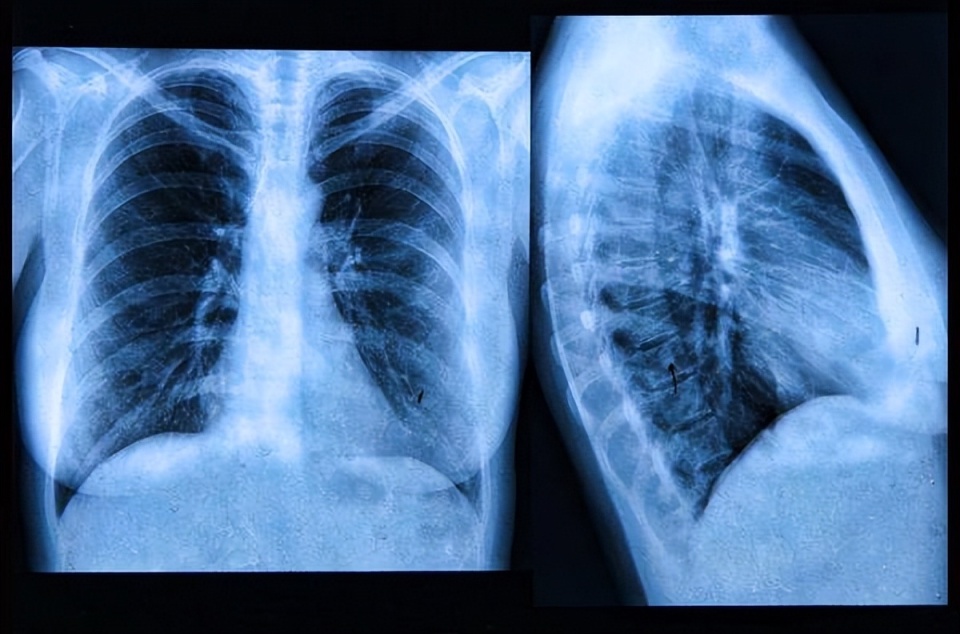

是继续治疗,还是摆烂等死?一旦查出肺癌晚期,还有必要治吗?

肺癌是我国发病率和死亡率最高的恶性肿瘤,且发病率呈逐年上升趋势。

由于体检普及率低,防癌体检不规范,大部分患者就诊时已经到了比较晚的阶段。

对于晚期肺癌患者,此时癌细胞已经转移。

通常情况下,由于个体差异,非小细胞肺癌患者未经治疗的死亡率,结果显示:未经治疗的非小细胞肺癌患者死亡率非常高,平均寿命只有7.15个月,也就是半年。

晚期肺癌如果不治疗,意味着放弃生存的希望,会加速病情,甚至加速死亡。

不同病理类型和治疗方法的晚期肺癌生存期不同,晚期小细胞肺癌,即晚期神经内分泌癌,预后最差,进展迅速,治疗有限。

只能用传统化疗,晚期小细胞肺癌生存期往往不到半年。

目前对晚期肺鳞癌可采用免疫治疗联合化疗,可适当提高生存期,晚期肺鳞癌的生存期通常在一至一年半左右。

目前晚期肺腺癌的治疗方法最多,尤其是靶向治疗,大约50%的晚期肺腺癌患者有靶向治疗的机会,生存期可达2~3年左右